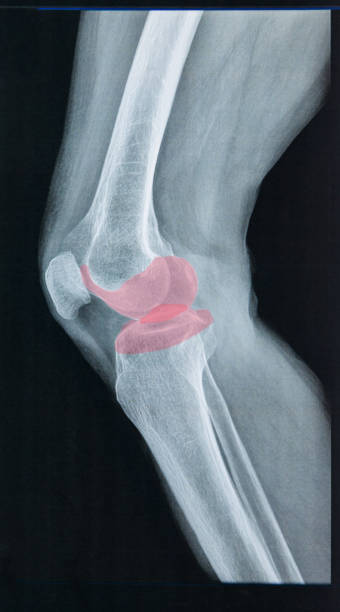

전방십자인대 파열에 의한 무릎 통증

전방십자인대는 무릎을 지탱하는 중요한 인대 중 하나입니다. 이 인대가 파열되면 무릎이 불안정해지며, 걷거나 달리는 등의 운동 시 무릎이 흔들리거나 무력감이 느껴집니다. 무릎 통증, 부종, 불안정감 등의 증상이 나타나며, 복합적인 치료가 필요합니다. 치료에는 수술적 치료, 전문가의 지도하에 진행되는 재활 운동 등이 포함됩니다.